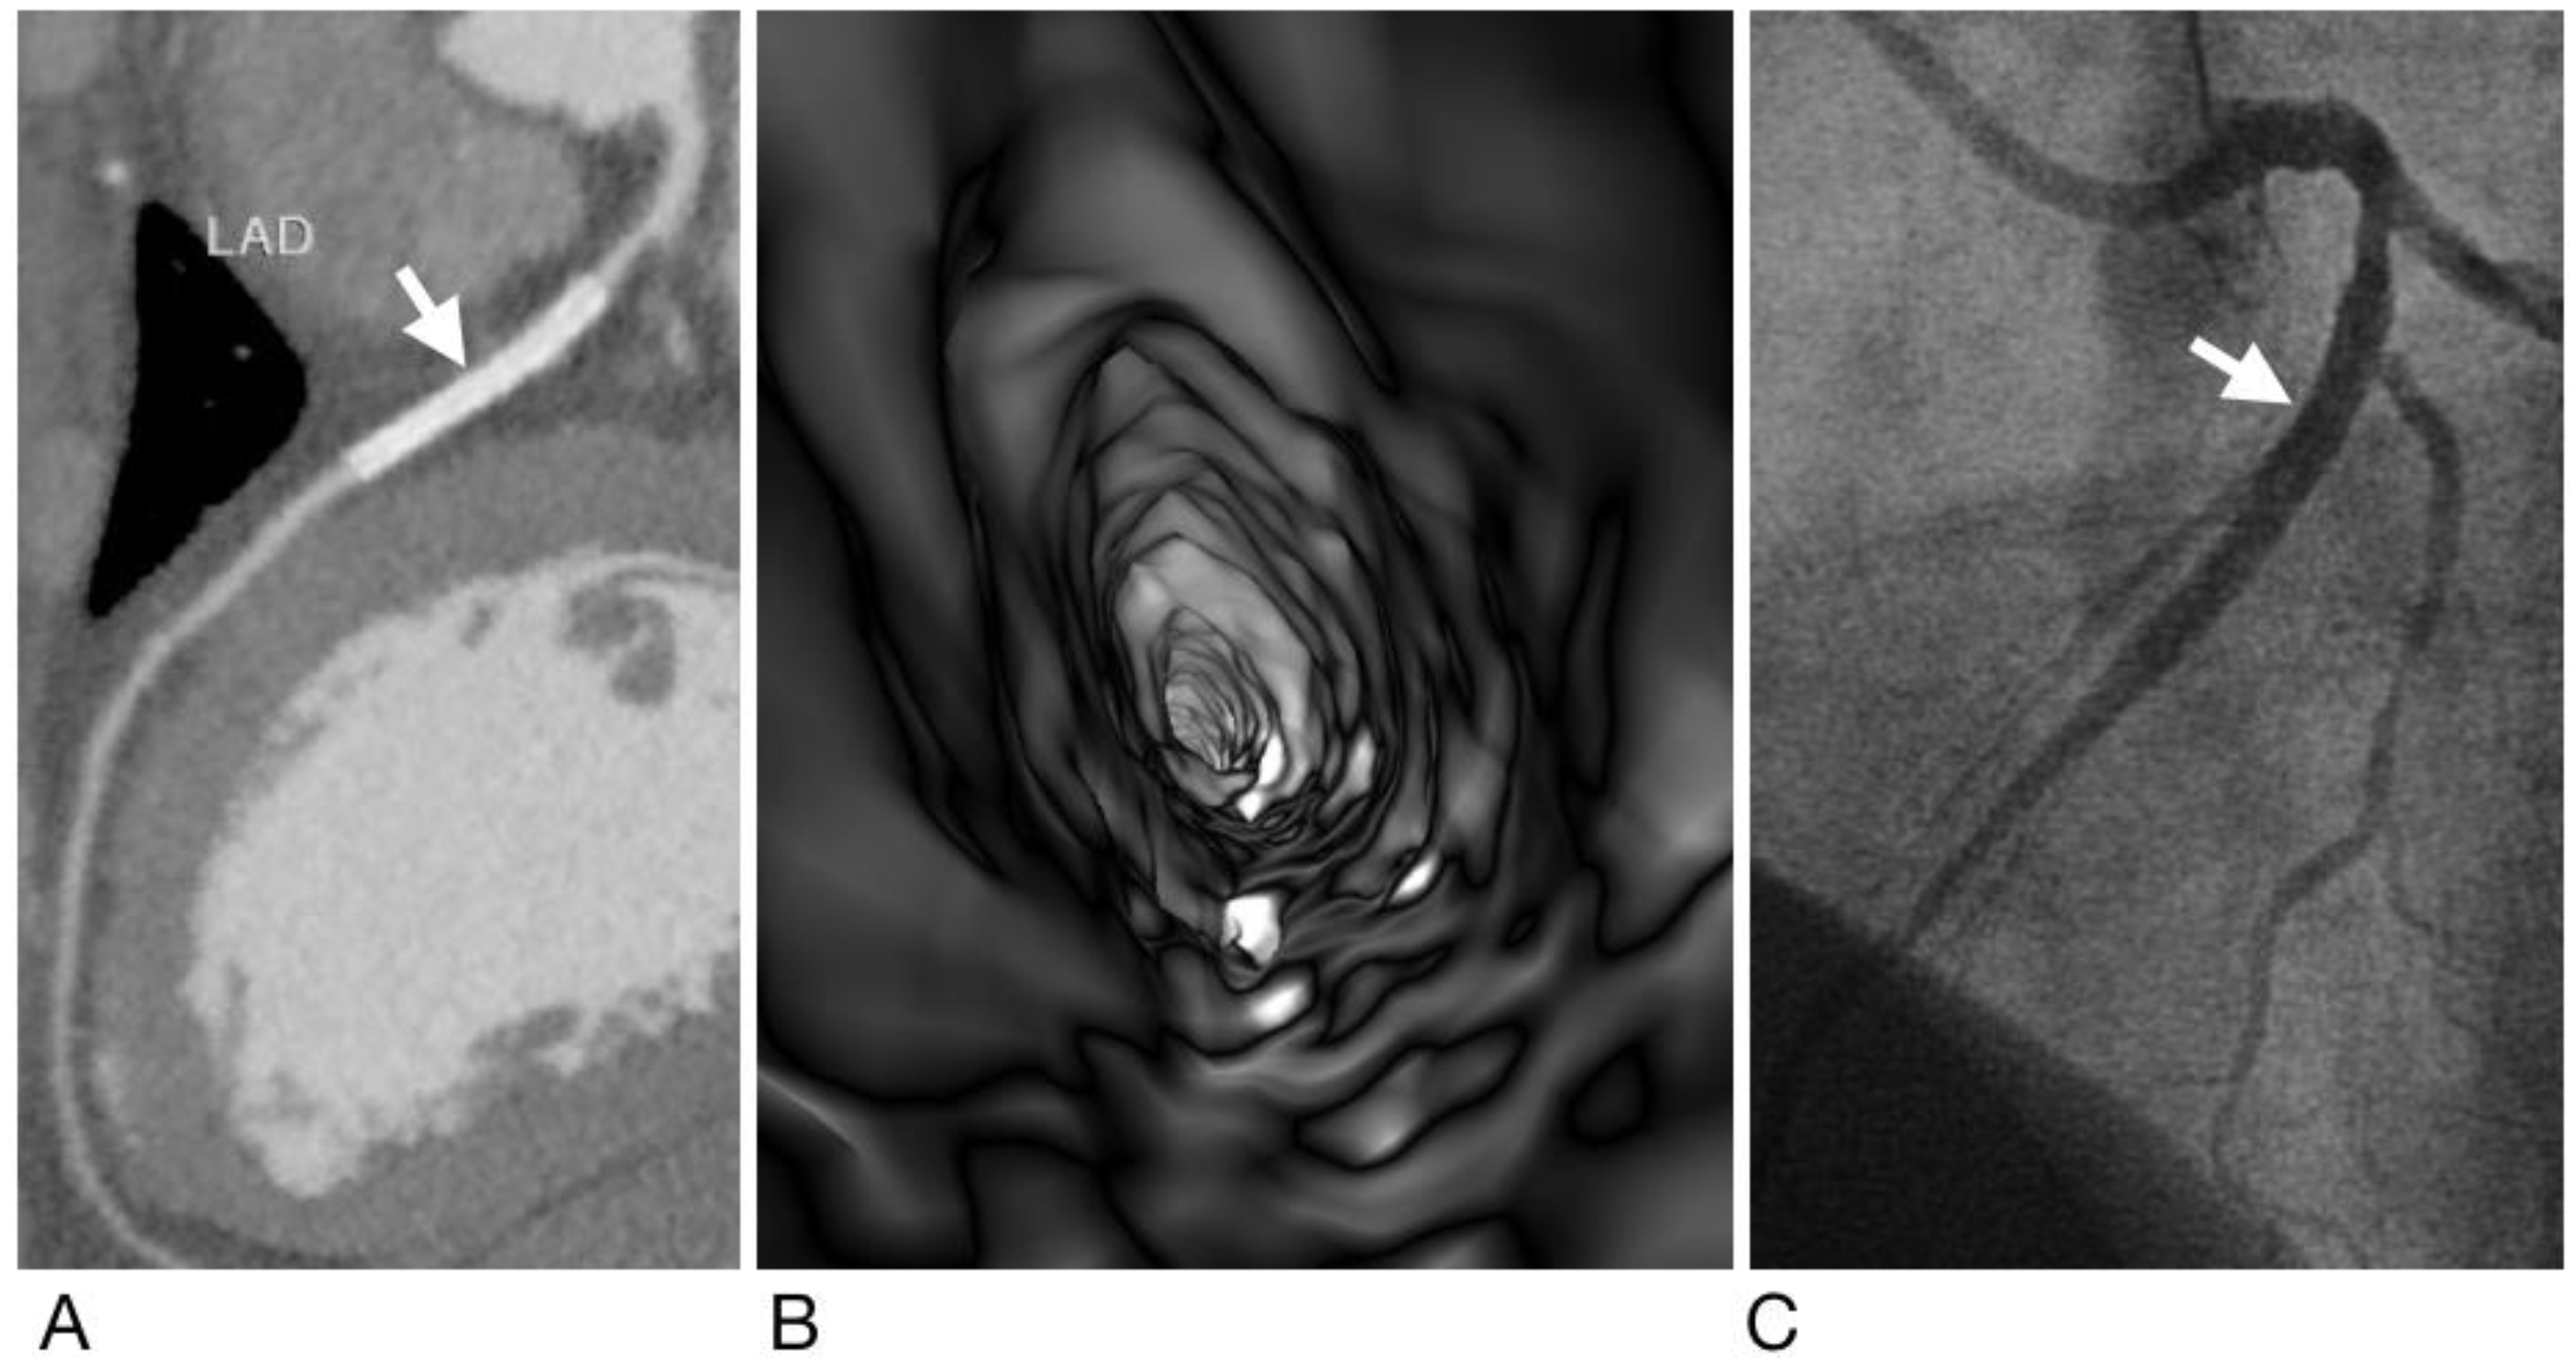

- Sun, Z.; Dimpudus, F.J.; Nugroho, J.; Adipranoto, J.D. CT virtual intravascular endoscopy assessment of coronary artery plaques: A preliminary study. Eur. J. Radiol. 2010, 75, e112–e119. [Google Scholar] [CrossRef] [PubMed]

- Xu, L.; Sun, Z. Virtual intravascular endoscopy visualization of calcified coronary plaques: A novel approach of identifying plaque features for more accurate assessment of coronary lumen stenosis. Medicine 2015, 94, e805. [Google Scholar] [CrossRef] [PubMed]

- Sun, Z.; Xu, L. CT virtual intravascular endoscopy in the visualization of coronary plaques: A pictorial essay. Curr. Med. Imaging Rev. 2017, 13, 154–161. [Google Scholar] [CrossRef][Green Version]

- Sun, Z. Coronary CT angiography in coronary artery disease: Correlation between virtual intravascular endoscopic appearances and left bifurcation angulation and coronary plaques. Biomed. Res. Int. 2013, 2013, 732059. [Google Scholar] [CrossRef]